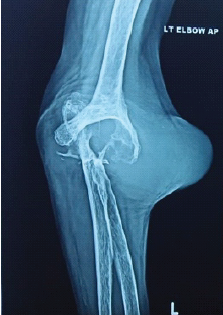

Letter to the Editor: Revisiting the “Ice Cream Scoop” Sign in Adult Elbow Tuberculosis: Extending Beyond the Pediatric Population

Nadeem Akhtar Qureshi

………………………………p.555-556